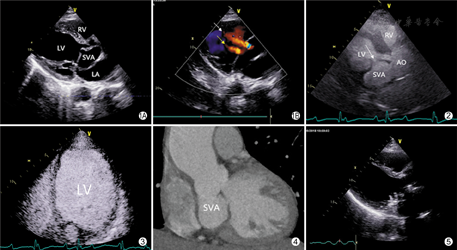

患者男,47岁,因"活动后气短2个月"入院。查体:心率64次/min,血压159/77 mmHg(1 mmHg=0.133 kPa),叩诊心浊音界向左侧扩大,心浊音界左侧最远点位于第五肋间左锁骨中线外0.5 cm处,主动脉瓣听诊区可闻及3/6级收缩期喷射性杂音及舒张期泼水样杂音。超声检查:左房、左室增大,升主动脉扩张;主动脉无冠窦呈囊袋样向下延续至二尖瓣前叶近瓣尖部,并与二尖瓣前叶粘连,囊袋大小约61 mm×33 mm,破口位于左室流出道侧,宽约9 mm;彩色多普勒示舒张期可见囊腔内血流分流入左室流出道,并于主动脉瓣及二尖瓣瓣口见大量反流(图1)。左室心腔造影显示:右房、右室、左房、左室依次显影后,造影剂自升主动脉进入囊袋,再经破口进入左室流出道,囊袋内可见充盈缺损(图2)。左室心肌造影所见:左心室各节段未见造影剂充盈延缓及减低(图3)。冠状动脉CTA检查所见:冠状动脉管腔未见狭窄及扩张。主动脉无冠窦见不规则囊袋状向下突出影,大小约3.6 cm×5.7 cm×4.1 cm,升主动脉管腔扩张,宽约5.4 cm(图4)。确诊后立即行手术治疗,术中所见:主动脉无冠窦形成窦瘤,向后累及二尖瓣前叶,形成囊袋,囊袋内血栓形成,向前突出于左心室流出道,主动脉瓣膜毁损,瓣口明显关闭不全,切开右心房、房间隔,探查二尖瓣前叶僵硬增厚,遂行Bentall及二尖瓣机械瓣置换术。切除主动脉瓣移送病理检查,病理描述为:退变的瓣膜组织,间质伴有粘液变性,散在慢性炎细胞浸润。患者术后复查心脏超声提示:人工血管血流通畅,瓣膜功能未见异常,心脏结构及功能良好(图5)。

本病例为无冠窦窦瘤破入左室流出道,并与二尖瓣前叶粘连,导致二尖瓣前叶变形,该种情况在主动脉窦瘤破裂中极其罕见。首次经胸超声心动图检查考虑为无冠窦窦瘤形成,但尚不能排除囊袋样结构来源于二尖瓣可能。进一步行左心超声造影检查示造影剂自升主动脉进入囊袋,后经破口进入左室流出道,囊袋内可见充盈缺损,由此可以推断囊袋样结构为主动脉窦瘤,并且窦瘤内已有血栓形成。冠状动脉CTA检查排除了冠脉病变并进一步证实了上述结论。左心超声造影对本病例诊断具有重大意义,心腔造影可以观察到血液灌注顺序,确定囊袋样结构来源于主动脉窦瘤而非二尖瓣,并能提供血栓形成的证据;心肌造影可以评价心肌微循环灌注情况,通过评估心肌血流量,可准确判断冠状动脉微循环障碍。左心超声造影对于行程复杂的主动脉窦瘤具有特殊诊断意义,可显示窦瘤与周围结构的关系,并可直接观察窦瘤是否破裂,为外科手术决策提供可靠证据。